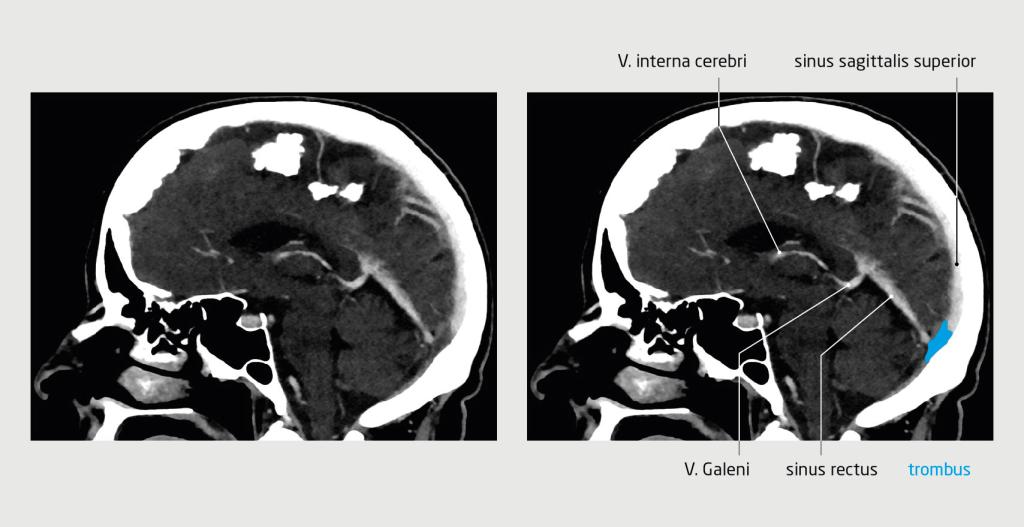

Figuur 2

Cerebrale veneuze sinustrombose

Figuur 2 | Cerebrale veneuze sinustrombose

Sagittale CT-scan van de hersenen van een 63-jarige vrouw waarop na intraveneuze toediening van contrastmiddel veneuze sinustrombose te zien is op de overgang van de sinus rectus naar de sinus transversus.

Vanwege het klinisch beeld en het vermoeden van trombose na vaccinatie bepaalden wij geen D-dimeerconcentratie, maar verrichtten wij gericht beeldvormend onderzoek. Na intraveneuze toediening van contrastmiddel was op een CT-scan van het abdomen trombose te zien van de linker V. renalis en V. adrenalis (figuur 1). Een CT-scan van de hersenen met contrast toonde in de linker hersenhelft veneuze sinustrombose op de overgang van de sinus rectus naar de sinus transversus (figuur 2).